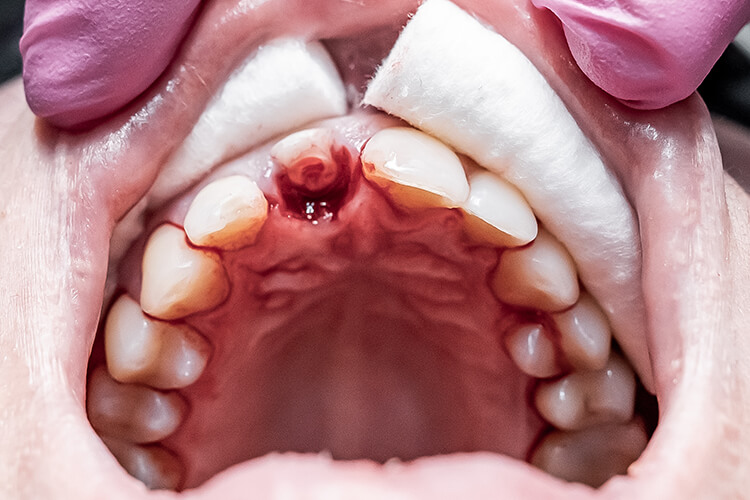

Если с зубами 1.2 и 2.1 особых вопросов не возникало, то зуб 1.1 был расколот на три части и имел обнаженный нервно-сосудистый пучок. Прежде чем предложить варианты лечения, потребовалась рентген-диагностика. На снимке врач увидел корни зубов целые, перелом коронковой части зуба 1.1, проходящий по пульповой камере.